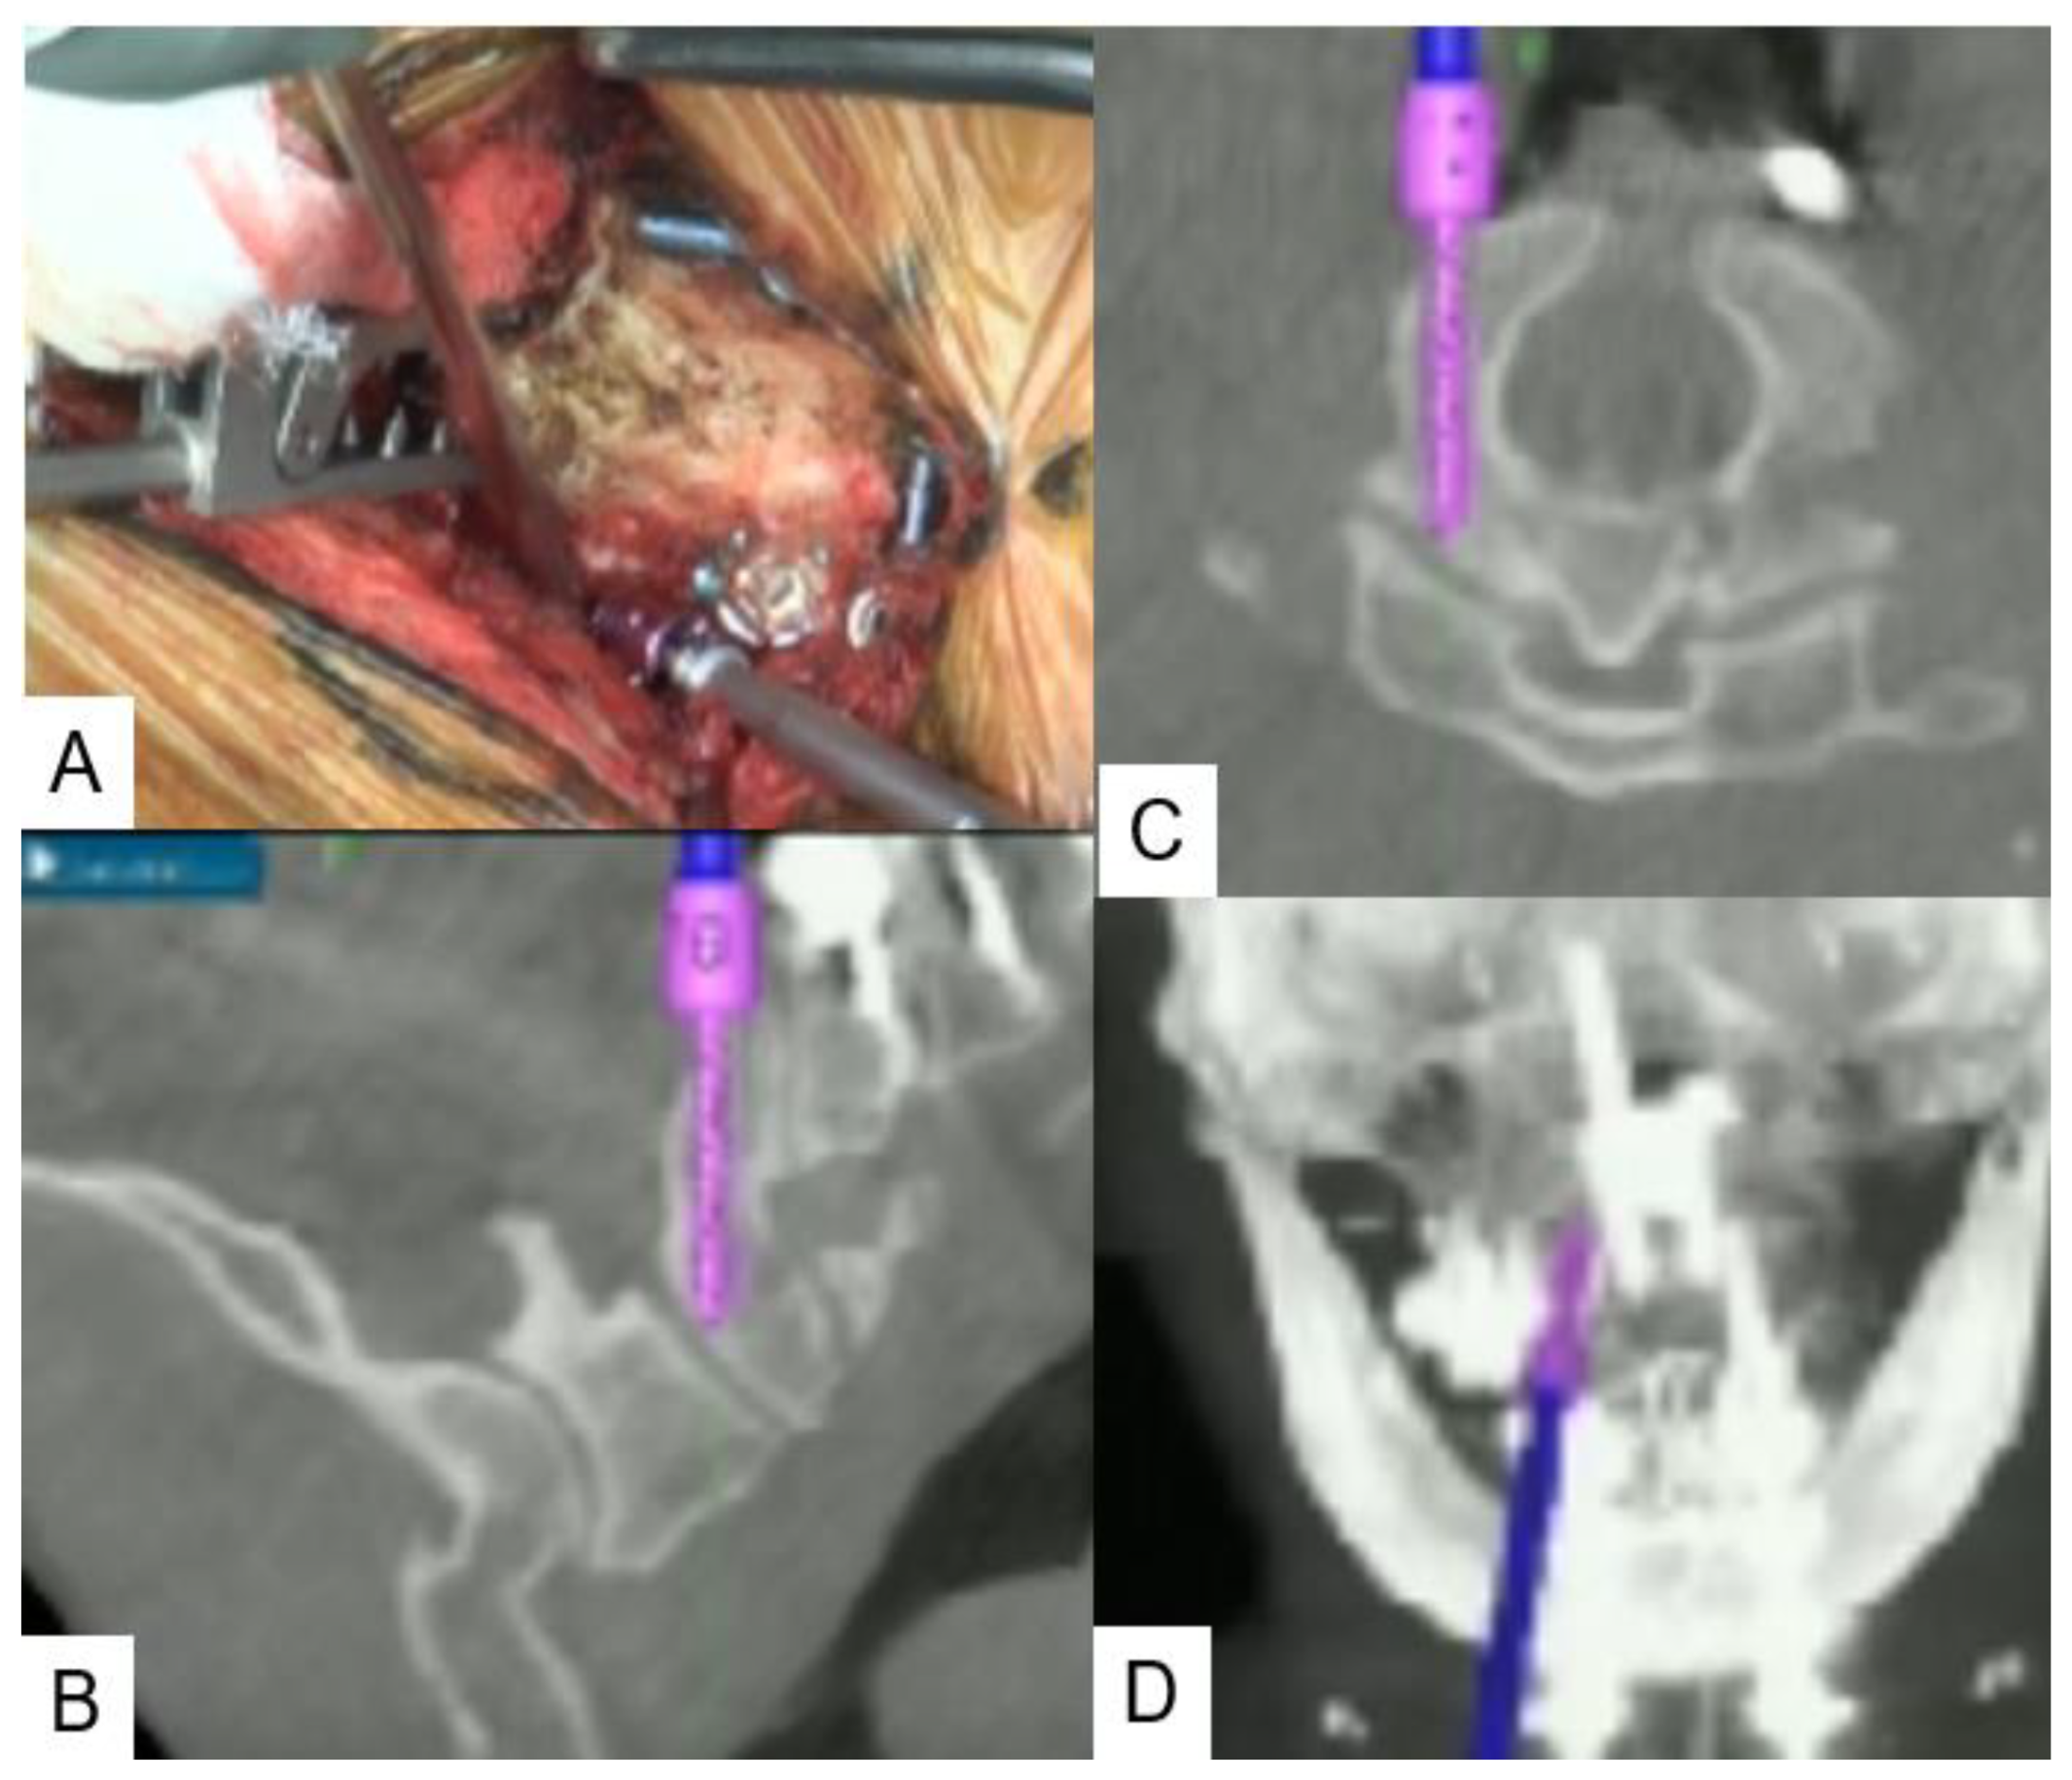

2.4. Surgery

3. Operative Procedure

3.2. C2 Pedicle Screw

3.3. C1 LMS